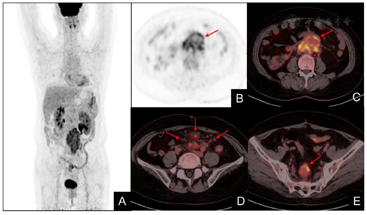

腹部增强CT示(图1):腹膜后软组织肿块,包埋推挤邻近血管,增强明显强化,考虑淋巴瘤,左侧肾盂-输尿管扩张积液。18F-FDG PET/CT示(图2):腹膜后团块状软组织病变(腹主动脉周围至髂血管分叉水平),邻近下腔静脉、双侧髂总动脉起始处及左侧输尿管受累;肠系膜间隙、直肠周围脂肪间隙、骶前间隙多发大小不等的肿大淋巴结,以上病变均呈FDG代谢增高,SUVmax 2.0-8.3,多考虑自身免疫性疾病。

实验室检查方面,RPF急性反应期ESR和CRP经常升高,但仍缺乏特异性的血清标志物。目前,计算机断层扫描(CT)和磁共振成像(MRI)是RPF的首选检查手段,典型表现为腰4-5椎体旁包裹腹主动脉和下腔静脉生长的软组织肿块,常侵犯邻近输尿管导致肾积水[5]。对比增强扫描病变强化程度可以表示RPF炎症活性,急性期高于慢性非活动期,但仍无法准确反映RPF受累区域的代谢活性[6,7,8]。在本案例中,CT发现腹膜后软组织占位,包埋推挤邻近血管,初步考虑淋巴瘤,与之不符的是典型淋巴瘤强化并不显著,然而该病例增强呈明显强化,误诊原因可能主要与局部成像无法准确评估全身受累情况的局限性有关。值得注意的是,相比CT或MRI,18F-FDG PET/CT具有更高的灵敏度,不仅可以真实地反映炎症活性程度、指导临床穿刺活检,还可用于RPF类固醇治疗的疗效评价[9,10]。此外,18F-FDG PET/CT在RPF与腹膜后恶性肿瘤(淋巴瘤或转移瘤)的鉴别诊断方面也具有很大的帮助[11]。本例患者18F-FDG PET/CT提示腹膜后团块状软组织病变(图2),不仅FDG代谢程度低于常见的腹膜后恶性肿瘤(如淋巴瘤),而且病变分布特征及其临床表现也不相符,因此多考虑自身免疫性疾病。